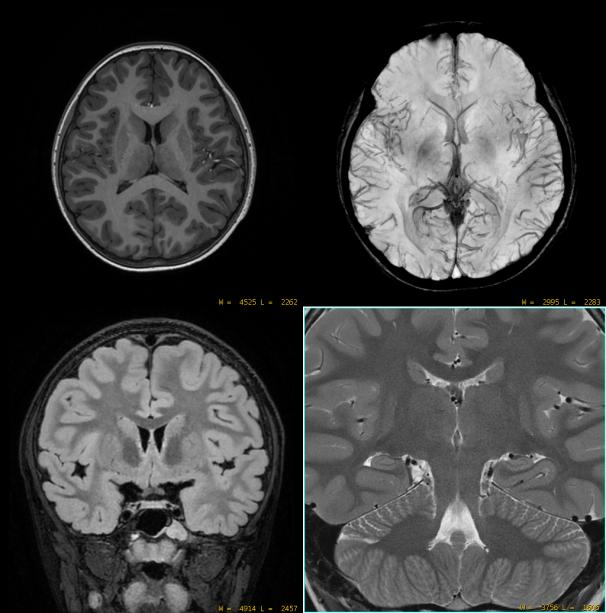

今年7月5日,3.0T磁共振设备正式投入临床及科研工作至今,多位患者从中受益。设备具备高清弥散、MAGIC(一种一站式弛豫定量技术,一次扫描获多组不同对比度图像和多种弛豫定量数据)、全脑静音血管成像、骨关节成像、四维流心血管磁共振成像(4D FlowCMR)、压缩感知等技术。

和普通磁共振相比,它的分辨率和信噪比明显提高,能够带来更高的图像质量,从而更早发现微小病变。

3.0T磁共振设备检查成像分辨率和信噪比明显提高,可更早发现微小病变。